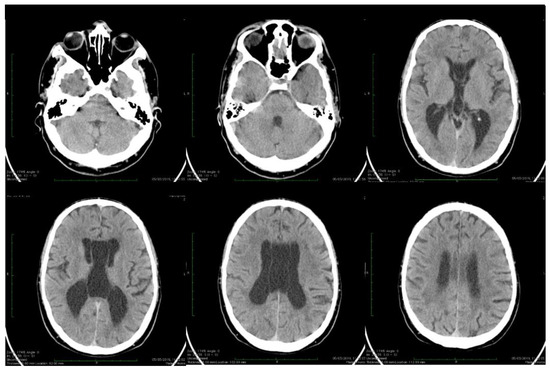

| Stoian et al. (our own case) | Case report | Male/4.5 months | Tonic seizures; later in evolution a left facial hemi spasm | 31 years | Reduced visual acuity (myopia), one and a half syndrome with left abduction nystagmus, left facial hemi spasms, divergent strabismus, flaccid tetra paresis, bilateral inconstant Babinski sign, gait instability, truncal ataxia, | Mild facial dysmorphism with thin upper lip and slightly spaced teeth | Social isolation, bradypsychia, bradylalia, echolalia, minimal linguistic baggage, behavioral stereotypes, MMSE17 points | Cryptorchidism | EEG: Poor unmodulated alpha activity, frontal intermittent theta activity; sharp waves and sharp peaks on the left central, parietal and temporal derivations | Brain CT: generalized sufferance pf white matter; cavum septum pellucidi, enlarged ventricular system, cerebral and cerebellar atrophy. Brain MRI performed before hospital admission: severe cerebral and cerebellar atrophy, vermis hypoplasia, supratentorial and infratentorial demyelinating lesions, cavum septum pellucidi, severe enlargement of the CSF spaces | Valproic acid, later replaced with levetiracetam and after a while with brivaracetam | The seizures disappeared under treatment being seizure-free since childhood; a left facial hemi spasm occurred lately |